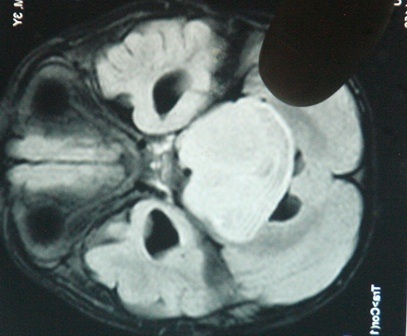

Theo đó, bệnh nhân P.H.H.H (SN 2009, trú tại tỉnh Gia Lai) nhập viện cách đây 6 tuần với các triệu chứng bệnh u não nặng. Em Hoàng có các biểu hiện như nhức đầu, nôn mửa, đi đứng khó khăn, bước đi hay loạng choạng phải có người dìu, mắt bị lác, tay chân yếu, nói không rõ và ngọng. Khối u nằm ở vùng thân não là vị trí không thể mổ được mà phải xạ trị. Được nhận định là khối u quá lớn, có kích thước 4x4x5cm nằm ở vị trí thân não, nơi hiểm ác nhất của não bộ.